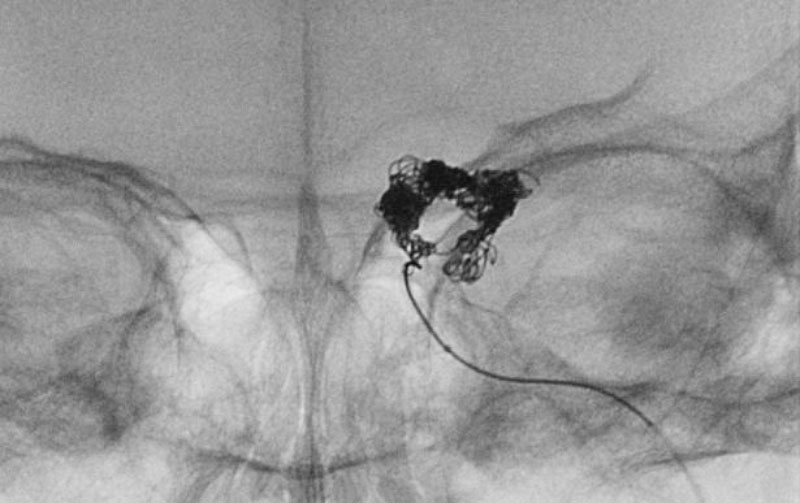

No.1591 手術中

'25年10月

硬膜動静脈瘻

50代

救急外来